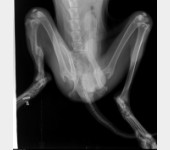

Leoś przebywał długie lata w schronisku w Raciborzu. Nikt Leosia nie chciał adoptować , taki był wycofany , bał się ludzi a w szczególności mężczyzn , co sami na sobie odczuliśmy jeżdżąc na wizyty zapoznawcze do hotelu w Gliwicach gdzie został przetransportowany. Leoś skradł nasze serca. Pomimo nie małych wątpliwości podjęliśmy decyzję o adopcji Leona i to była najlepsza decyzja. Leoś to piesek o wspaniałym charakterze , zrobił bardzo duże postępy , bez nas nigdzie się nie ruszy. Jesteśmy zmuszeni prosi o pomoc. Niestety okazało się , że nasz pupil zaczął mieć problemy z chodzeniem. Diagnoza lekarska była jednoznaczna, bez operacji Leoś przestanie chodzić. A opis lekarza ortopedy brzmiał tak : CAŁKOWITE ZWICHNIĘCIE STAWÓW NADGARSTKOWYCH , CAŁKOWITE ZERWANIE WIĄZADEŁ , DAWNE ZŁAMANIE KOŚCI PISZCZELOWEJ Z NIEPRAWIDŁOWYM ZROSTEM. LICZNE ZWYRODNIENIA STAWÓW, Załączam zdjęcia RTG .

Obecnie Leoś jest po operacji łapy przedniej lewej co ilustrują zdjęcia.